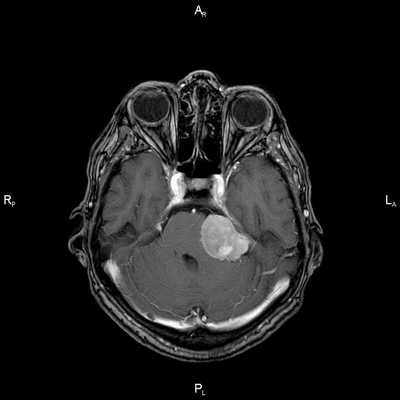

Диагноз: Онкология. Менингиома мосто-мозжечкового угла

При МРТ головного мозга в левом мосто-мозжечковом углу определялось больших размеров округлой формы внемозговое патологическое образование, с четкими ровными контурами, широким основанием, прилежащее к твердой мозговой оболочке. После внутривенного контрастирования отмечалось равномерное, выраженное усиление интенсивности МР-сигнала от вышеописанного образования, а также твердой мозговой оболочки. Пациенту был поставлен диагноз (менингиома левого мосто-мозжечкового угла).